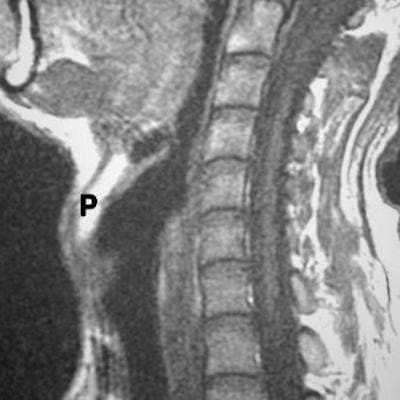

МР-снимок глотки и гортани

Киста шеи (щитоязычного протока) представлена на двух МР-снимках в разных режимах, имеет гиперинтенсивное содержимое на Т2 ВИ, четкий контур

Объемное образование в области гортани (стрелки): проекция спереди и сбоку